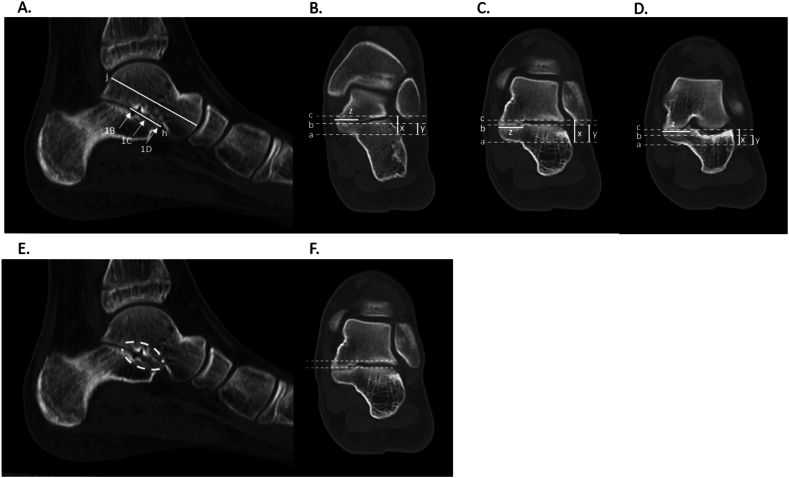

Methods: A retrospective review was conducted of TCC patients with preoperative computed tomography (CT) at a single institution from 2010 to 2022. Three independent raters reported sagittal TCC length relative to the talus. Raters further quantified TCC coronal depth and height across distal, middle, and proximal thirds of the TCC relative to the sustentaculum talus. This guidance directs two osteotomy cuts through the coalition directly into the normal lateral subtalar joint for complete and accurate excision of the coalition. CT measurement inter-rater reliability was determined using intra-class correlation.

Results: Twenty-seven patients (16 male), average age 13.9 ± 2.4, met study criteria. TCCs were located on the right lower extremity in 10/27 cases. Sixteen/twenty-seven coalitions were horizontal, 10/27 was down sloping, and 1/27 was upsloping relative to the joint line. Substantial agreement was achieved between three raters (mean average measures intraclass correlation 0.781). The mean coalition length in the sagittal plane was 21.2 ± 6.0 mm, covering 49.6 ± 23.2% of the talar length.

Key concepts: (1)To date, very little in the way of intraoperative planning for TCCs has been proposed in the literature, even though advanced imaging has been widely used preoperatively.(2)Our method of mapping coalitions on preoperative CT may assist with intraoperative resection. Additionally, this method demonstrates the three-dimensional variety that can be expected in surgical excision of these coalitions.(3)Neither the medial to lateral depth nor the distance proximal from the sustentaculum talus was uniform as the coalitions were thickest centrally and tapered both proximally and distally.